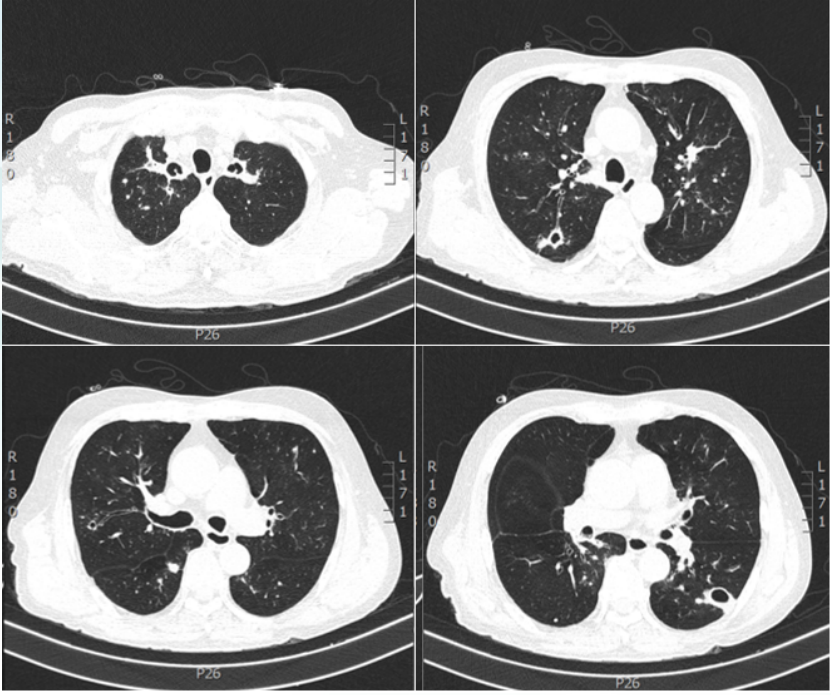

• 胸部CT: 双肺空洞, 结节, 部分伴晕征(图1)

图片

1  患者入院后胸部CT(2023-05-08)